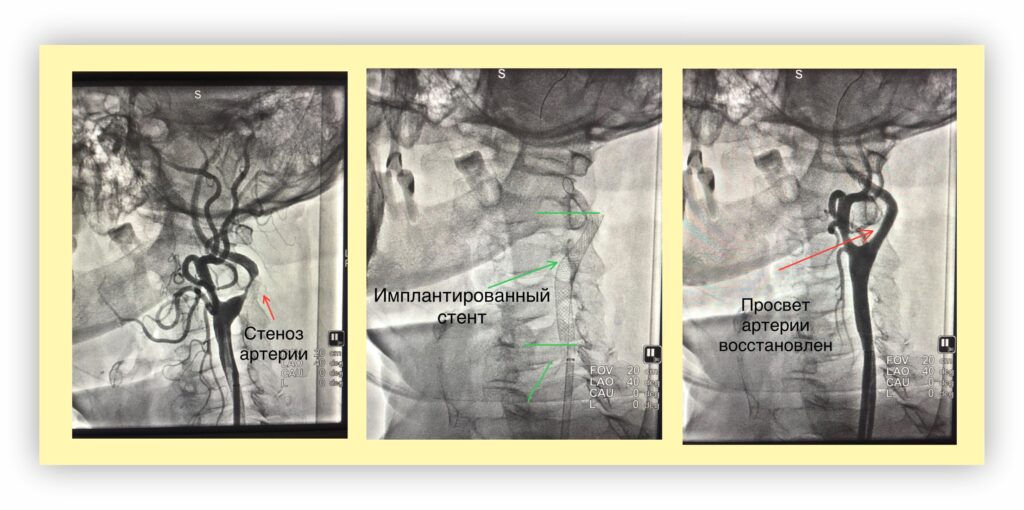

В отделении функционирует ангиографический комплекс, который предоставляет возможность проводить высокоточные исследования и вмешательства. Рентгенохирургические методы диагностики и лечения являются современными и эффективными подходами в медицине, позволяющими врачам проводить процедуры с минимальным вмешательством и высокой степенью безопасности для пациентов.

Ангиографический комплекс в Кинешме позволяет проводить диагностику различных заболеваний, включая сердечно-сосудистые патологии, а также осуществлять лечение с использованием современных технологий. Это открывает новые горизонты для пациентов, которые могут получать квалифицированную медицинскую помощь на месте, не выезжая в другие города.